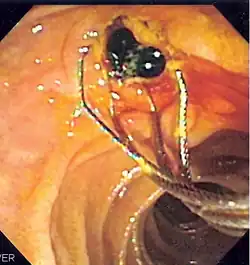

![]() Duodenoscopic image of two black pigment stones extracted from common bile duct after sphincterotomy | |

The patient is sedated or anaesthetized. Then a flexible camera (endoscope) is inserted through the mouth, down the esophagus, into the stomach, through the pylorus into the duodenum where the ampulla of Vater (the union of the common bile duct and pancreatic duct) exists. The sphincter of Oddi is a muscular valve that controls the opening to the ampulla. The region can be directly visualized with the endoscopic camera while various procedures are performed. A plastic catheter or cannula is inserted through the ampulla, and radiocontrast is injected into the bile ducts and/or pancreatic duct. Fluoroscopy is used to look for blockages, or other lesions such as stones.[8][9]

When needed, the sphincters of the ampulla and bile ducts can be enlarged by a cut (sphincterotomy) with an electrified wire called a sphincterotome for access into either so that gallstones may be removed or other therapy performed.[10]

Other procedures associated with ERCP include the trawling of the common bile duct with a basket or balloon to remove gallstones and the insertion of a plastic stent to assist the drainage of bile.[11] Also, the pancreatic duct can be cannulated and stents be inserted.